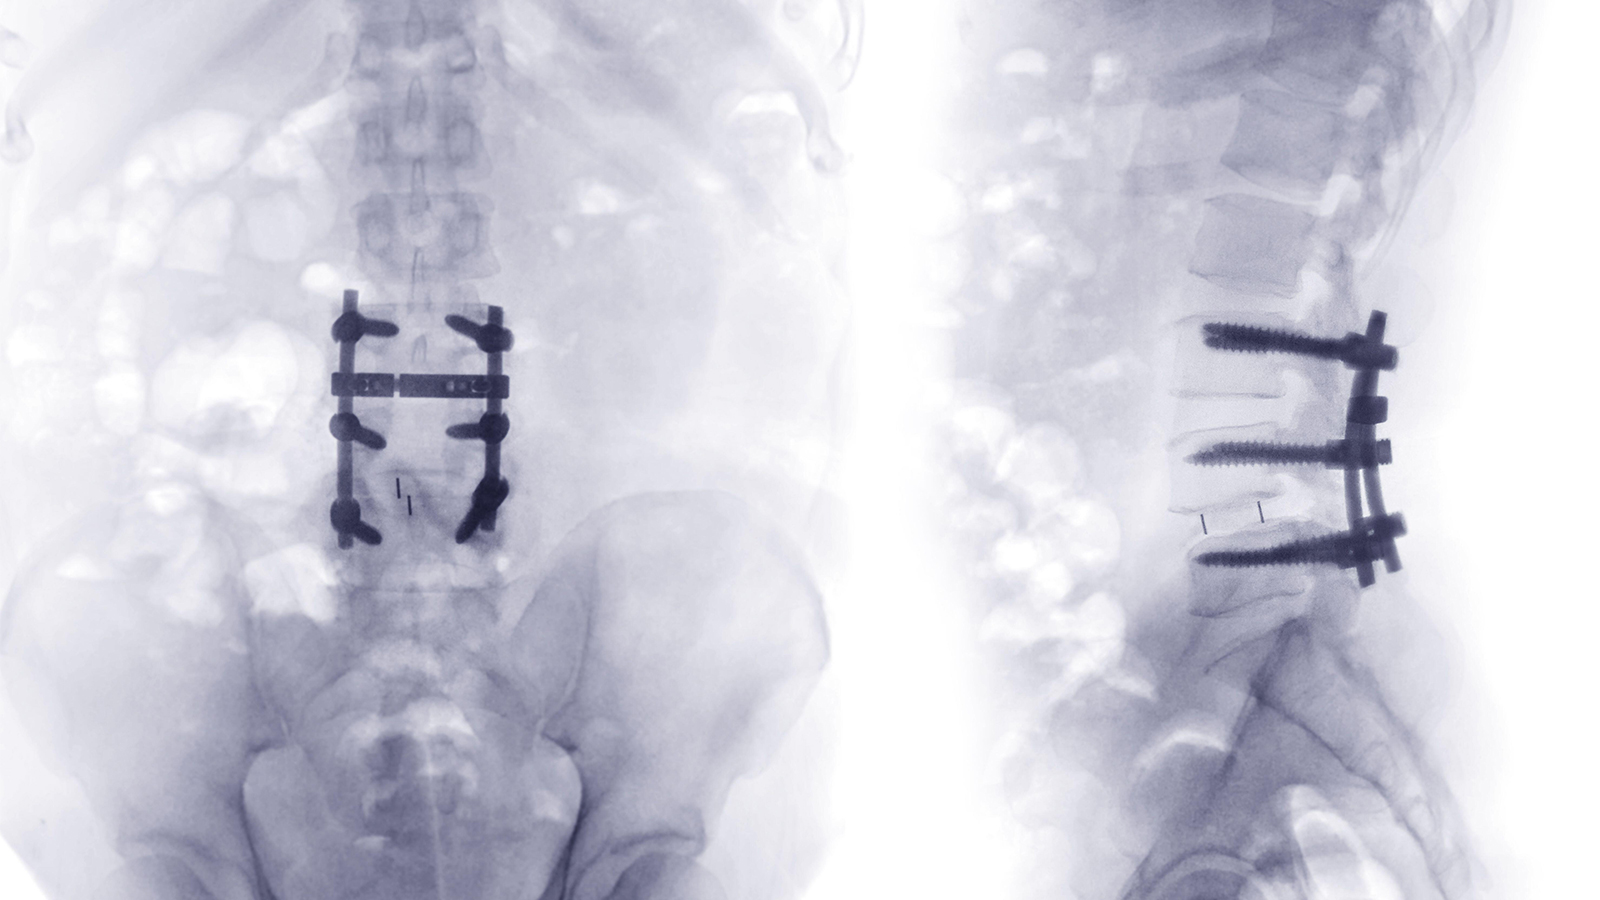

Spinal Surgery Redux: Advancing Our Approach to Back Pain

(MedPage Today) — Lower back pain has been the leading cause of years lived with disability since 1990, and it continues to be a significant concern for public health on a global scale. In the U.S., 72.3 million adults currently suffer from chronic…